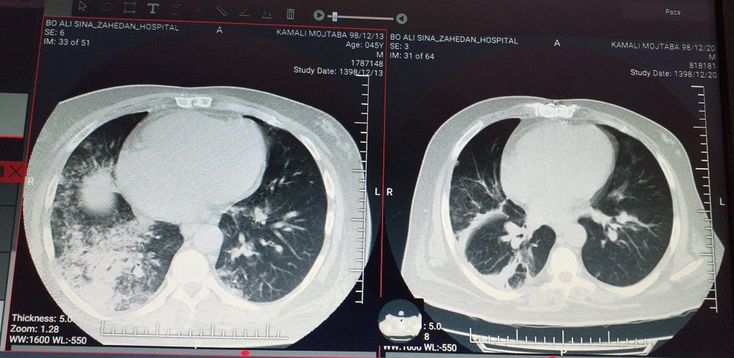

A 65 year old male with dyspnea and non productive cought and fever and chilling has been admitted with COVID 19 pneumonia. Here is the chest ct scan before and after treatment.

What do you think? the right is the follow up one.